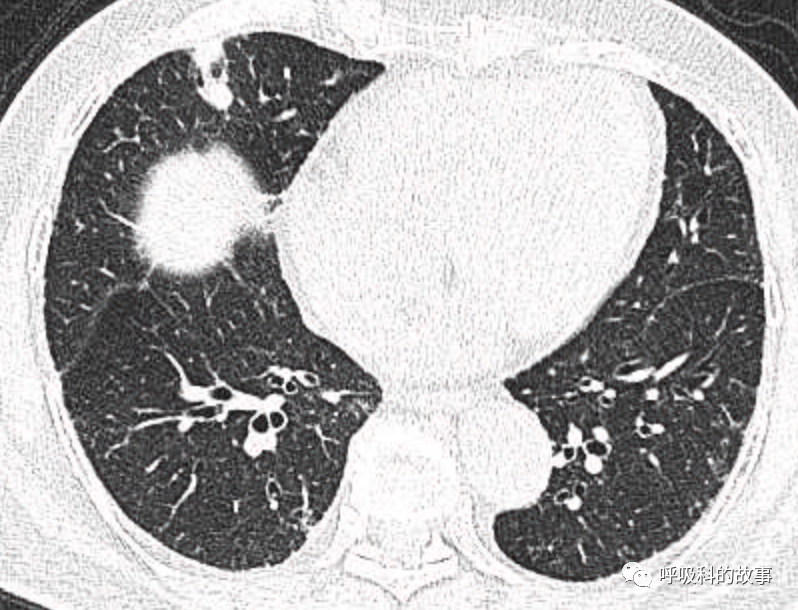

可是就在今年初,患者曾住在某院某科室,因为其他内科疾病住院。当时肺部CT也发现了在右中叶内侧段的高密度实变影,由于影像很类似肺炎,因此当成肺炎治疗。

图12-14:该患者各个角度的影像图像

(上下滑动查看全部图片)